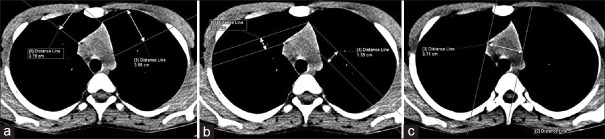

Patients and methods: This is a retrospective study done after taking approval from the Institutional Ethics Committee. Patients undergone CT scans of the thorax were identified from our database. All evaluations were done in non-contrast CT scans. Patients having underlying diseases that may have associated thymic abnormality were excluded. The appearance of thymus and the presence of fatty replacement were assessed. The size of thymus (length and thickness of right limb and left limb) and non-contrast CT Hounsfield unit (HU) value of thymic tissue were measured and compared in various age groups.

Results: Four hundred and fifty patients were included, 262 (58.2%) were male. Mean age was 33.6 ± 17.1 years, range (3 months-80 years). The size of thymus was observed to decrease with increasing age. The mean age of complete fatty replacement in our study was 45 years. Complete fatty replacement was noted in all cases with an age of more than 60 years. The most common shape was arrowhead, and the most common location was pre-aortic and para-aortic location. Non-contrast CT HU value was maximum in infants and gradually decreased with advancing age.